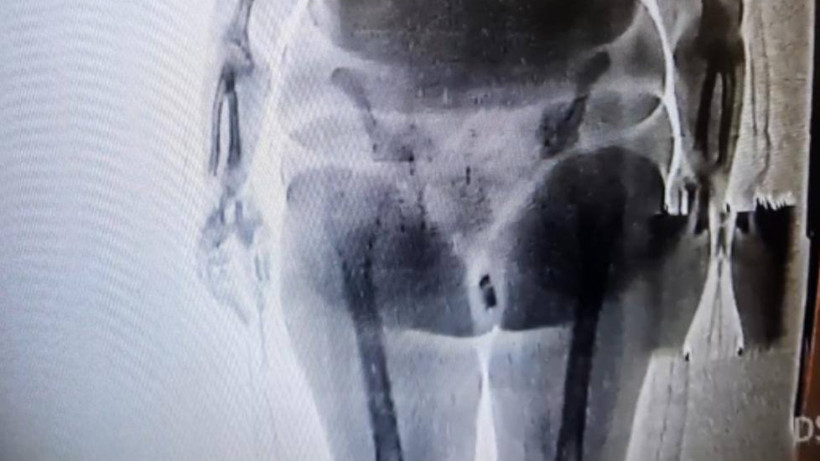

Женщина пыталась пронести в следственный изолятор телефон и SIM-карту, спрятав их в интимном месте. Она пришла на свидание со своим супругом, находящимся под следствием в СИЗО. При прохождении через рентген-устройство сотрудники увидели инородный предмет. После тщательного досмотра в женской комнате обнаружить предмет контролерами и медицинскими работниками не удалось. Как выяснилось в ходе изучения записи с камеры видеонаблюдения, женщина в комнате досмотра, до прихода медицинских работников, успела достать сверток и спрятать. В свертке были обнаружены телефон и SIM-карта.